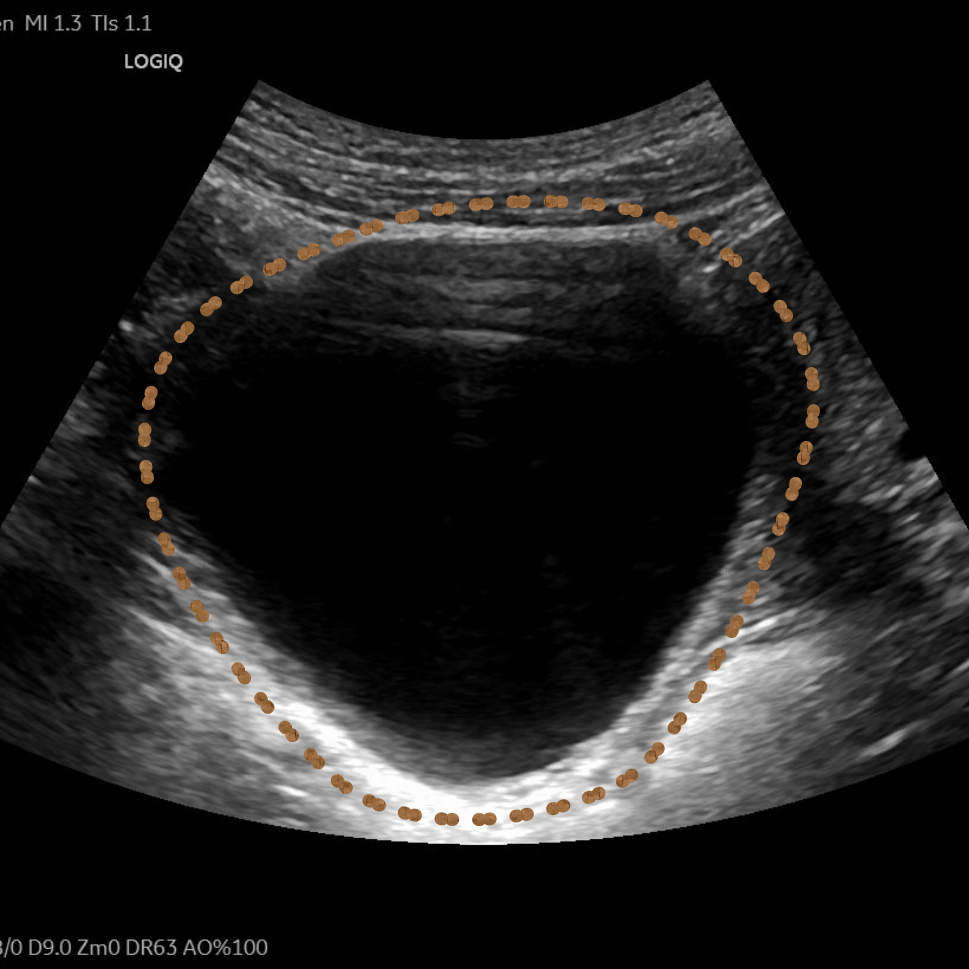

14岁女生小黄因小腹不适由母亲带至昆山市中医医院妇科就诊,超声检查后发现右附件区有一个8.0*7.2cm的巨大囊肿。由于正值初三备考的关键时期,如何解决囊肿还不能耽误复习迎考,这成了选择手术方式的关键点。

图片

▲小黄的影像学检查

超声介入团队联合妇科对患者进行全面综合评估后,认为超声引导下抽液硬化治疗是其最佳选择。待一系列术前常规检查后,在局部浸润麻醉下进行囊肿穿刺抽液硬化治疗。

整个治疗过程顺利,患者无明显不适,未影响其正常复习迎考。三月后腹部超声检查,右附件区囊肿已完全吸收。